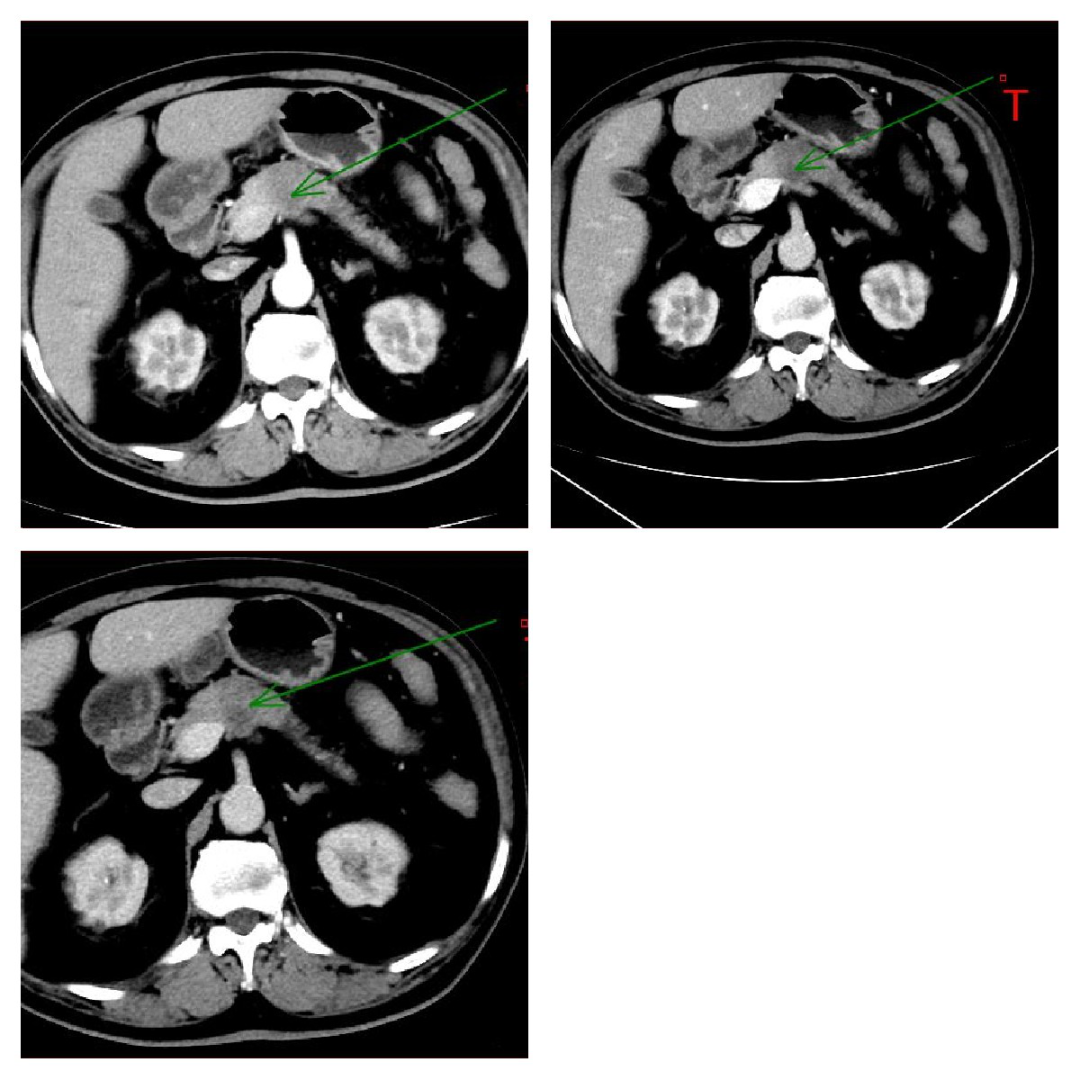

脉管癌栓:肝细胞肝癌容易发生脉管癌栓,ct 平扫显示为沿门脉走形区增宽;动脉期可见门脉走形区内不规则强化影;静脉期及延迟期强化减低。